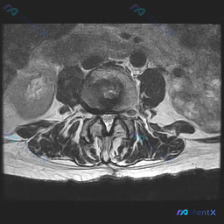

腰椎MRI读片分享,椎间盘突出的典型影像表现你能一眼认出来吗?

这是一份腰椎MRI T2加权轴位(横断面)影像,显示腰椎管层面,可见椎体后缘、椎间盘、硬膜囊、侧隐窝、后方椎板及关节突关节等结构,图像对比度正常,脑脊液呈高信号。

- 椎间盘:髓核T2信号减低(灰黑色),提示退行性脱水改变;椎间盘后缘向后方突出,呈广基底膨出/突出形态

- 椎管与硬膜囊:突出的椎间盘压迫硬膜囊前缘,形成明显压迹,硬膜囊从正常类圆形变成扁平状,前方脑脊液高信号区明显变窄甚至消失,是典型的椎管受压表现

- 侧隐窝与神经根:双侧侧隐窝都有不同程度狭窄,突出的椎间盘组织和双侧神经根关系密切,存在挤压可能

- 其他结构:双侧关节突关节对称性良好,无明显间隙异常或严重骨质增生;后方黄韧带无明显肥厚,无向椎管内突出